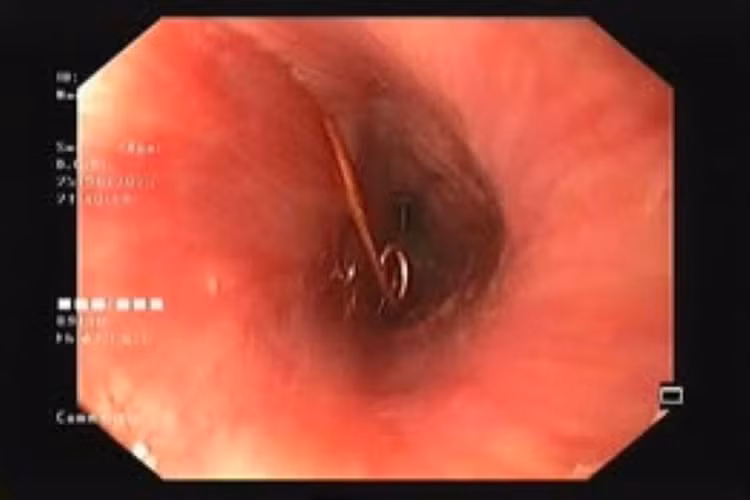

Tại Khoa Cấp cứu, qua thăm khám và hình ảnh nội soi, bác sĩ phát hiện cây kim băng dài khoảng 3 cm, đã bung ra thành hình chữ L và đầu nhọn đang ghim vào thành thực quản – gây nguy cơ thủng, chảy máu và nhiễm trùng rất cao.

Với sự khéo léo và phối hợp nhịp nhàng, các bác sĩ đã lấy dị vật thành công bằng phương pháp nội soi, tránh được một cuộc phẫu thuật phức tạp cho bé.

Thực hiện nội soi lấy kim băng dài và nhọn kẹt trong lòng thực quản bé trai ra ngoài - Ảnh BVCC